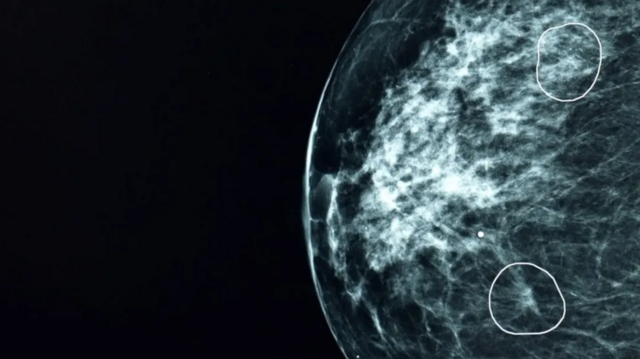

Duas áreas de preocupação destacadas por ferramenta de IA

Uma ferramenta de inteligência artificial testada pelo NHS, o serviço público de saúde do Reino Unido, identificou com sucesso pequenos sinais de câncer de mama que não haviam sido detectados por médicos.

A ferramenta, chamada Mia, foi testada em conjunto com médicos do NHS e analisou mamografias de mais de 10 mil mulheres.

Na maioria dos exames, Mia não identificou indícios de câncer, mas sinalizou com sucesso todos aqueles em que havia indícios apontados por médicos antes, além de outros 11 em que os médicos não haviam identificado tumores.

Nos estágios iniciais, o câncer pode ser extremamente pequeno e difícil de detectar.

A BBC acompanhou Mia em ação em um hospital do NHS. Foram mostrados à ferramenta tumores que eram praticamente invisíveis ao olho humano. Mas que, dependendo do tipo, podem crescer e se espalhar rapidamente.